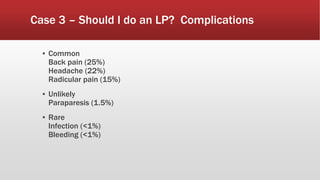

This document discusses various cases of collapse and syncope. It defines collapse as transient loss of consciousness with loss of postural tone and full recovery. Syncope is defined as loss of postural tone with or without loss of consciousness and full recovery. It then discusses the multiple potential causes of collapse and syncope including toxicological, cardiac conduction abnormalities, structural cardiac issues, autonomic dysfunction and more. It then goes through 9 case examples, discussing important questions to ask, potential tests and interventions for each case.